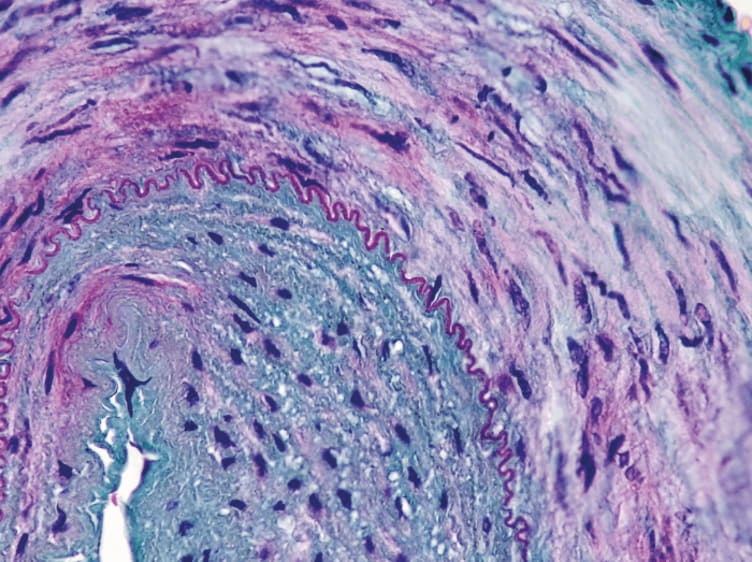

Hydrophilic Polymers

Hydrophilic polymers identified from a case of ischemic colitis in a patient with an aortic aneurysm repair. The polymers display a serpiginous configuration within vessels and a fuzzy and stippled basophilia on H&E (top) and are turquoise on colloidal iron (bottom).

Christina Arnold, The Ohio State University, USA.